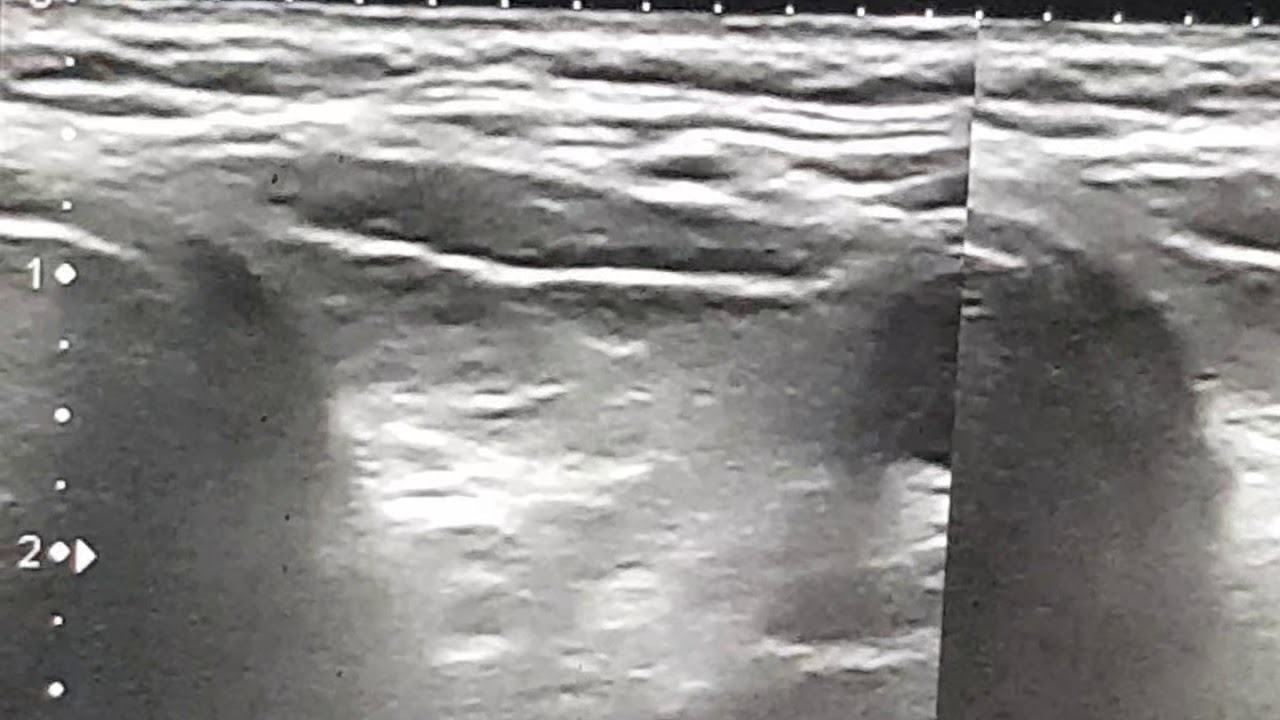

Predavanje o tumorima štitnjače u organizaciji sekcije mladih endokrinologa

ključne riječi: tumor, štitnjača, adenom, karcinom, papilarni karcinom, folikularni karcinom, medularni karcinom, jod, tireoidektomija, operacija